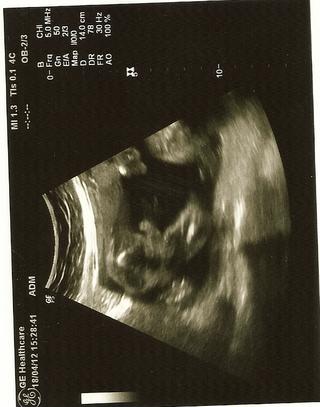

@miskachrumka tak uz sa asi nedaju cely pofotit len take kusky ako mame mi z dneska 🙂

aj mi ukazoval srdiecko,pecen chrbticu tvar nohy ruky a prstiky,ale nedali sa ratat,kedze ma kopal a mrvil sa aj pri sone 😀 😀

@porinka taka normalna jak vzdy vsetky mam 🙂 mozno mi to tak blbo naskenovalo len 🙂